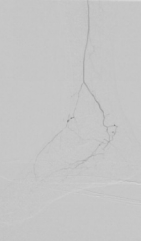

4. 开通胫前-足背动脉